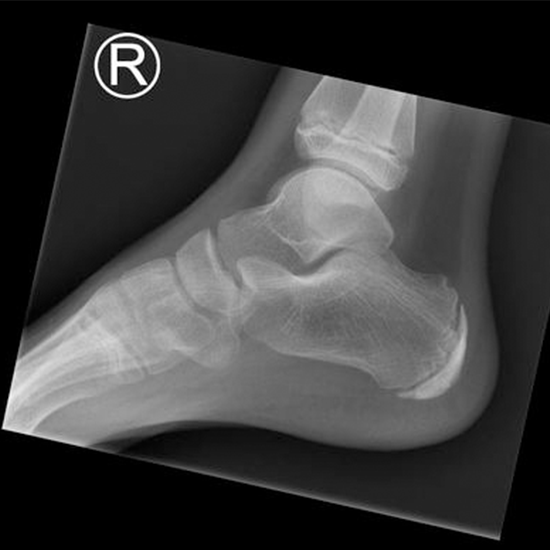

X-ray Right Heel AP/LAT

An X-ray of the heel is used to see the heel bone (calcaneum) and the surrounding soft tissues (skin and muscles).

• To diagnose fractures of the heel bone (calcaneum) and monitor the bone's healing once it has been set.

• To identify any infections, osteoporosis, malformations, or abnormal bone development.